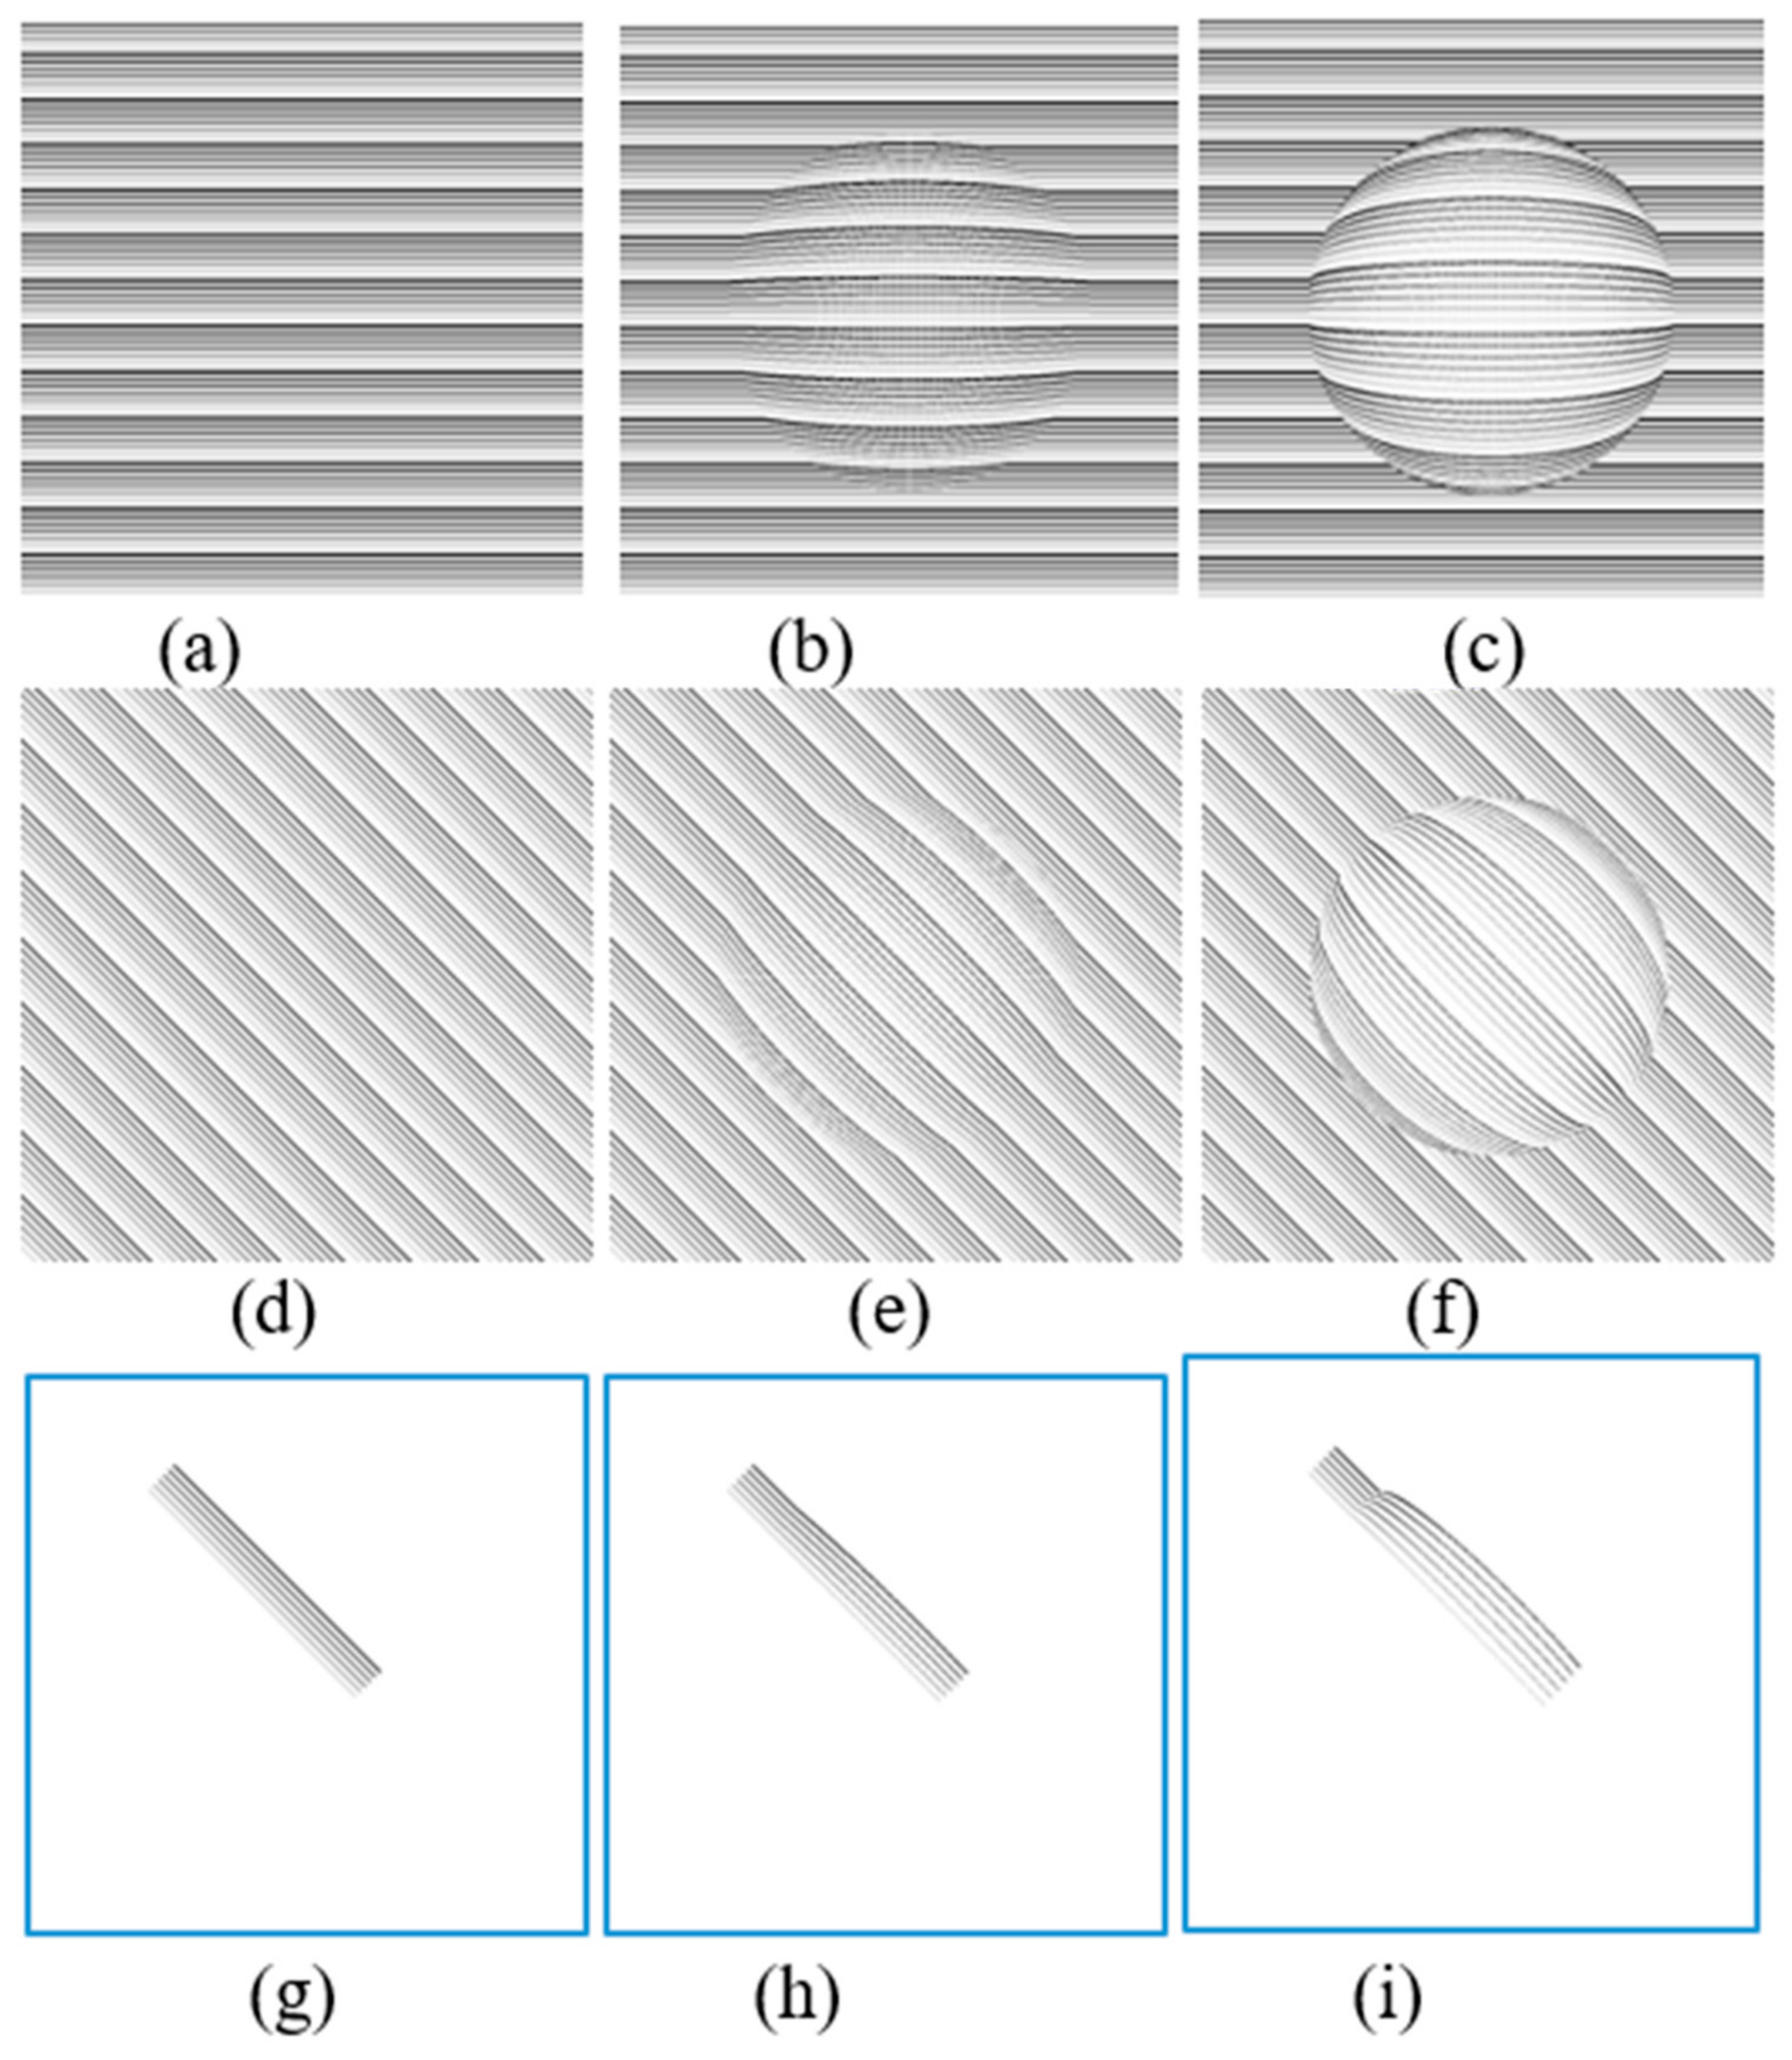

3.1. Effect of CSR in the Visual Field

3.2. Spherical Shape CSR Modeling

5.1. Simulation Results of CSR Modeling